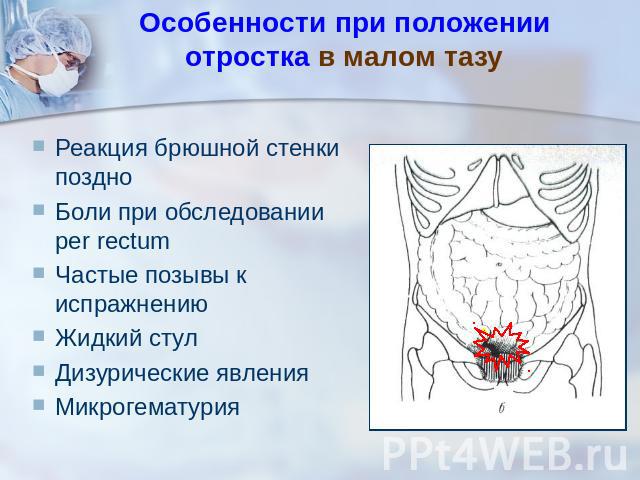

Боль в малом тазу у женщин: Причины и подходы к лечению